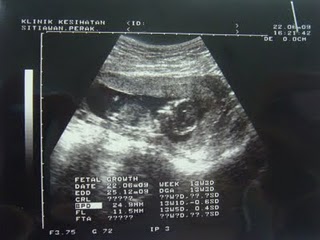

pemeriksaan bulanan

arini kena ke klinik stewan tuk cek perut...awal kitorg dh kua rumah...sbb bajet nk smpai b4 7.30pgi...pagi ni ade temujanji tuk minum ayo gula tuk kali kedua...so kena puasa dr kul 11.00 smlm...mmg terase laporpo nye...smpai je klinik terus ke blk tuk minum ayo gule...1st die amek drh dlu...disebabkan urat² aku comel² je..susah gak le misi tu nk cocok...tp berjaye jugak le..then dgn lajunye aku amek segelas ayo gula yg mmg aku idam²kan...hahaha...x smpai 5 minit abeh ayo tu...sedap sggh....lek umah t nk buat sndri laaa... :)

pas minum g kaunter cek bulanan lak...dpt no 3009...hmm...then cek cam biase la...cek bp...cek kencing...cek hb darah...tp kan...hb darah turun lagik dong.....10.3...n ayo kencing kotor la plak...terpakse la jumpe doc...hadoyaiii....kena amek no lain plak...dpt no 1015...ramai plak yg jumpe doc ari ni....xpe la..kena g buat ujian ayo kencing lg skali....then kul 10 aku g blk minum ayo gula tuk amek 2nd nye drh...result die len kali baru dpt...time tuk jumpe doc la plak....sempat kuar mkn dlu sbb aku dh kelaparan sgt dh...then dtg lek ke klinik...sgguh lame nk nunggu doc pggl...ade la dkt sejam lbh...smpai je turn aku....masuk le dlm blk..doc lain le plak..die scan perut nk tgk baby...so far so good la keadaan baby tu...pale baby dh kebawh...uri x tindih baby...tiada tanda kecacatan....tumbesaran baby mengikut due date...alhamdulillah....